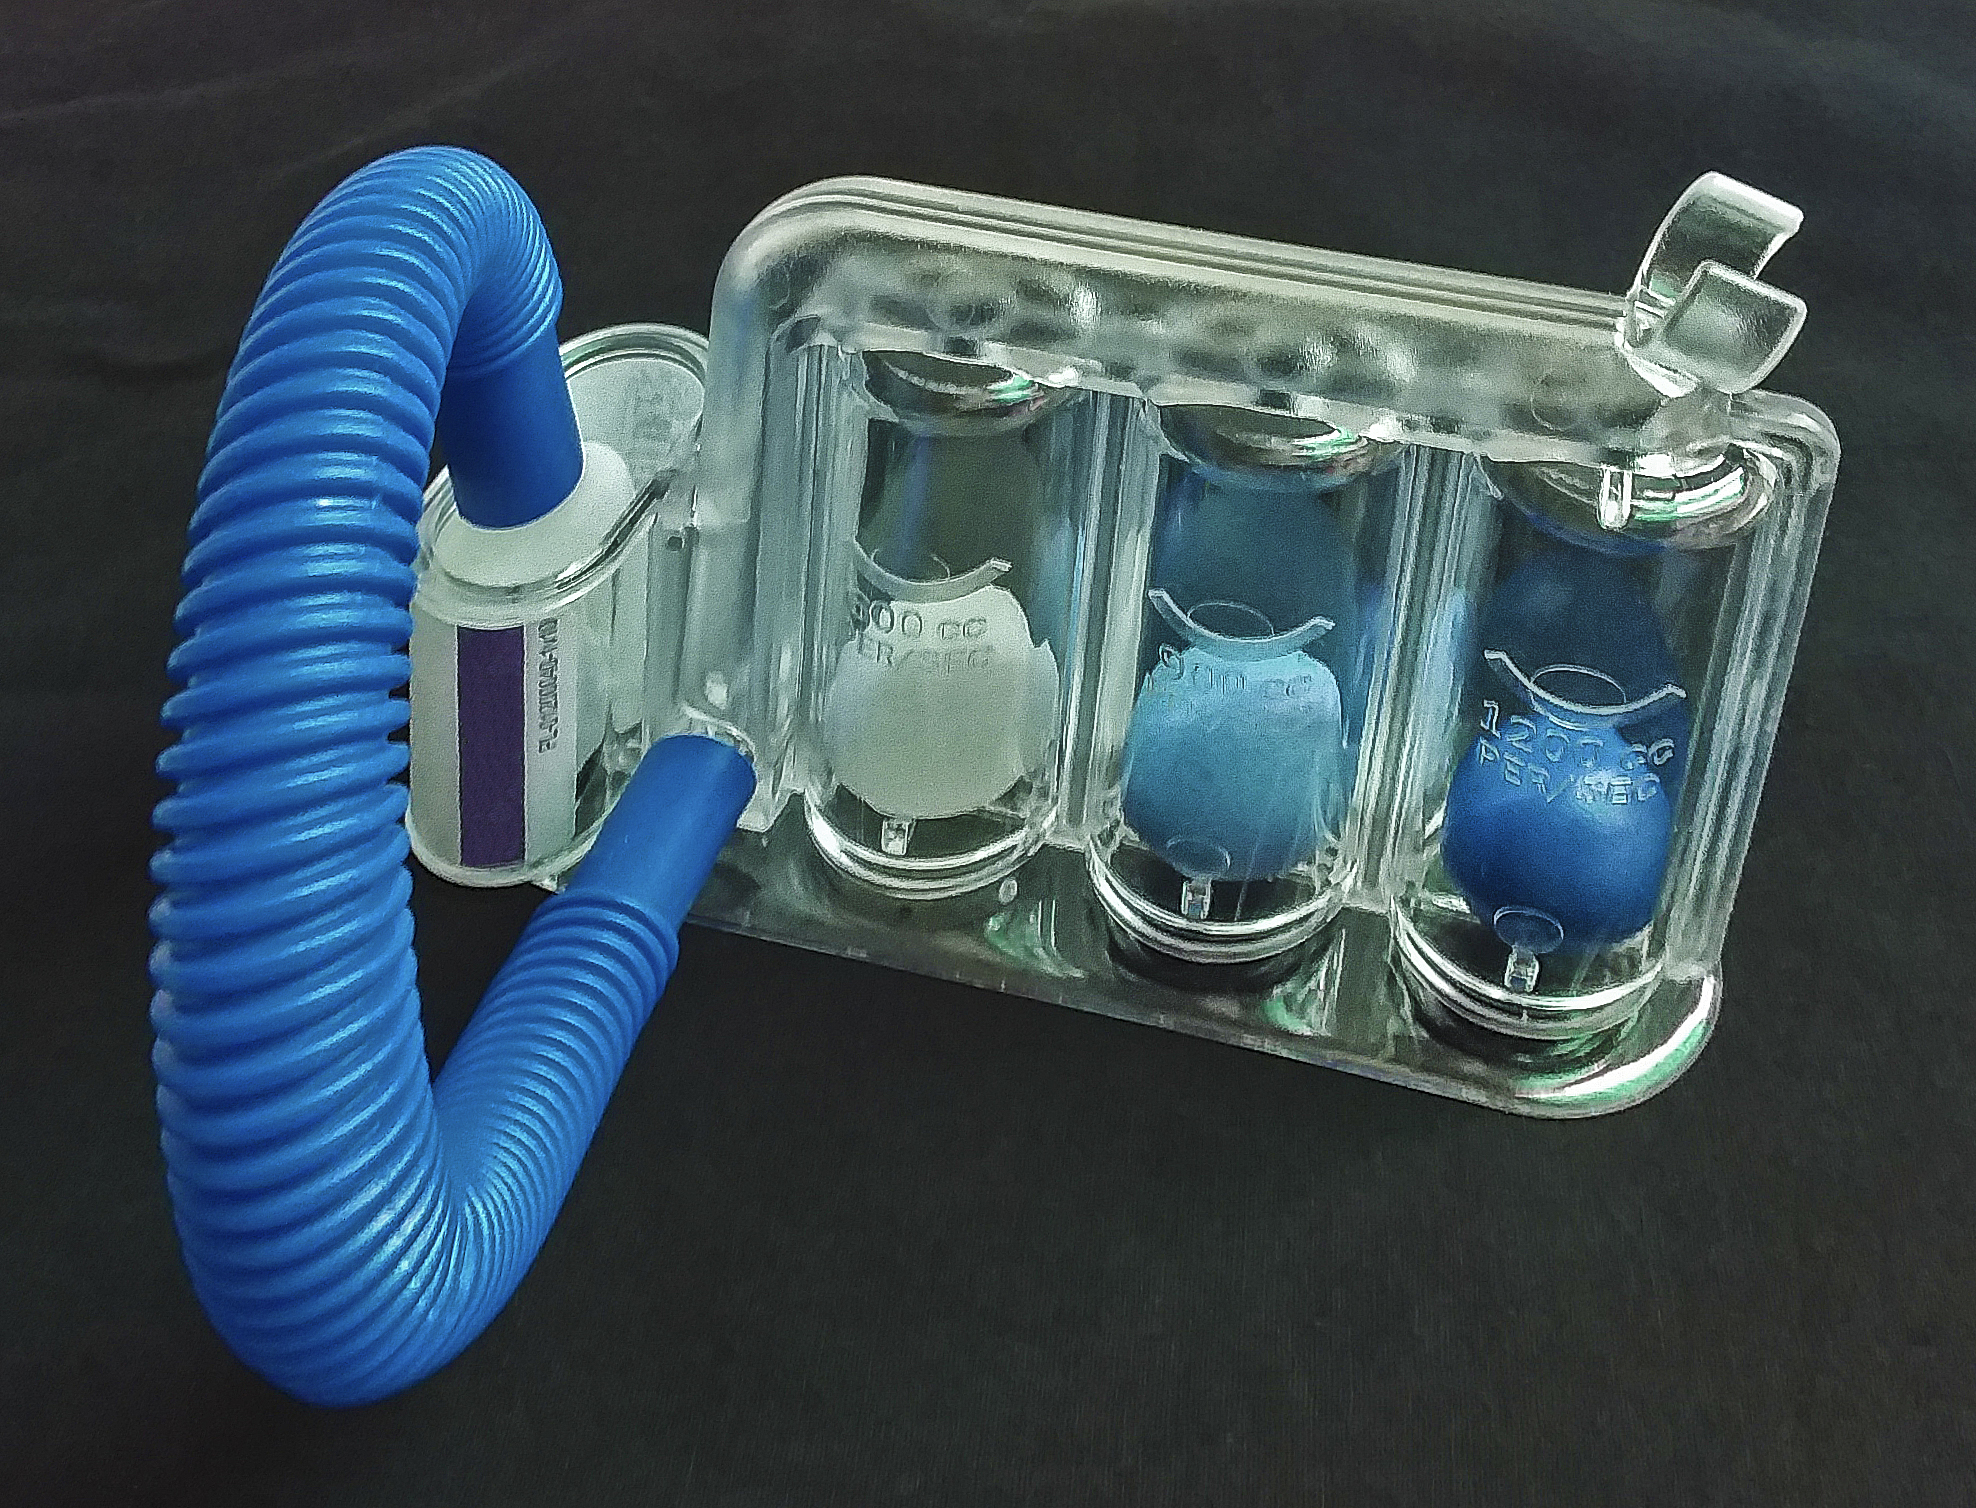

Mit diesem Tri-Ball-Atem-Therapie-Gerät - das mir meine mich gesundheitlich eng betreuende Schwägein Susanne noch empfohlen hat - kann ich die Intensität meines Atems üben